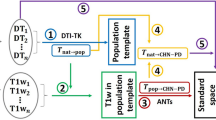

Definition of ROIs in standard space and space transformation procedure to each subject anatomical space

Definition of ROIs for studied tracts was made by replicating a set of predefined ROI by Mori et al. [8] that was employed successfully in subsequent work [7, 9, 20, 21]. These ROIs were drawn using the program MRIcron (http://www.mccauslandcenter.sc.edu/crnl/mricron/) on a reference anatomical image with spatial resolution of 1 × 1 × 1 mm3 in stereotactic space of the Montreal Neurological Institute (MNI) [22]. The ROIs were then transformed to each individual brain space automatically, using a programmed routine in MatLab v.7.7 (MathWorks, Inc.).

The reconstruction of the tracts of interest was possible using the deterministic method FACT and ROIs obtained for each subject by the transformation proceeding of reconstruction of the trajectory proposed for ten tracts of interest in each of the 84 subjects enrolled in the study. These tracts were classified for description in four functional categories: brainstem fibers and projection, association fibers, tracts of the limbic system and commissural fibers (See Additional file 1).

The tridimensional reconstruction of ten tracts of white matter was achieved in a representative sample of Cuban population. The protocol included ROIs in a native space of each individual and the tractography method known as FACT. The trajectories obtained agree with neuro-anatomic descriptions derivate from post-morten and other tractographic studies [8, 21, 24, 25].

The ROIs that defined tracts’s trajectories were drawn on anatomical reference image from MNI steoreotaxic space according to the anatomical description reported for Mori et al. [8] and validated for Wakana et al. [7, 21]. Our data probed their reliability. These authors drawn the ROIs on each individual brain; however, we drawn the ROIs on MNI space and automatically were transformed to native space of each individual allowing the optimization of ROIs procedure and diminish the time needed for their analysis and the inter-subject variability. Also this analysis begins from the total tracking of the all brain, and posteriorly the tracts were select using the ROIs. This approach produces a nice balance of fibers density [26] along the resultant tract giving reliability to the results.